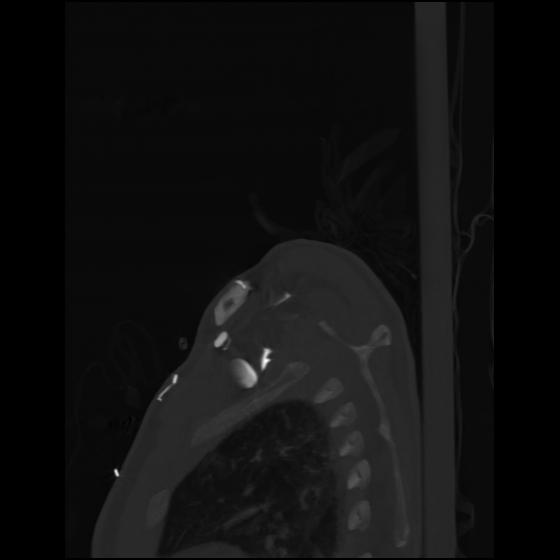

24 ANGIO,CE,Sag-MIP,5.000,ANGIO,Sag-MIP,